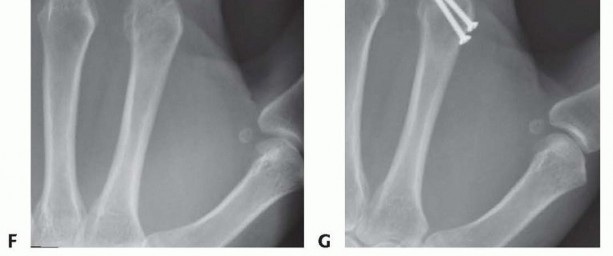

Once reduced, fixation can be achieved via crossed Kirschner wires or retrograde intramedullary pinning (the "bouquet" technique). However, the modern gold standard for minimally invasive fixation is the retrograde intramedullary headless compression screw. A small stab incision is made over the dorsal aspect of the flexed MCP joint. The entry portal is meticulously established in the articular "safe zone" of the metacarpal head—specifically the dorsal-ulnar or dorsal-radial collateral recess, strictly avoiding the central weight-bearing articular cartilage.

A guidewire is advanced down the medullary canal across the fracture site under fluoroscopic guidance. After confirming perfect rotational alignment and length, the canal is sequentially broached or drilled, and an appropriately sized headless compression screw is buried beneath the articular cartilage. This technique provides robust, load-sharing stability that allows for immediate, unrestricted active range of motion, vastly reducing the incidence of postoperative stiffness compared to traditional K-wire constructs.

Following definitive fixation, a rigorous fluoroscopic check is performed in multiple planes to confirm anatomical reduction, appropriate hardware placement, and crucially, to ensure no screws are penetrating the volar cortex excessively, which could tether the underlying flexor tendons. The tourniquet is deflated, meticulous hemostasis is achieved, and the extensor mechanism is meticulously repaired with fine absorbable sutures. The skin is closed without tension, and a bulky, well-padded dressing is applied, splinting the hand in the intrinsic-plus position.

Clinical & Radiographic Imaging Archive